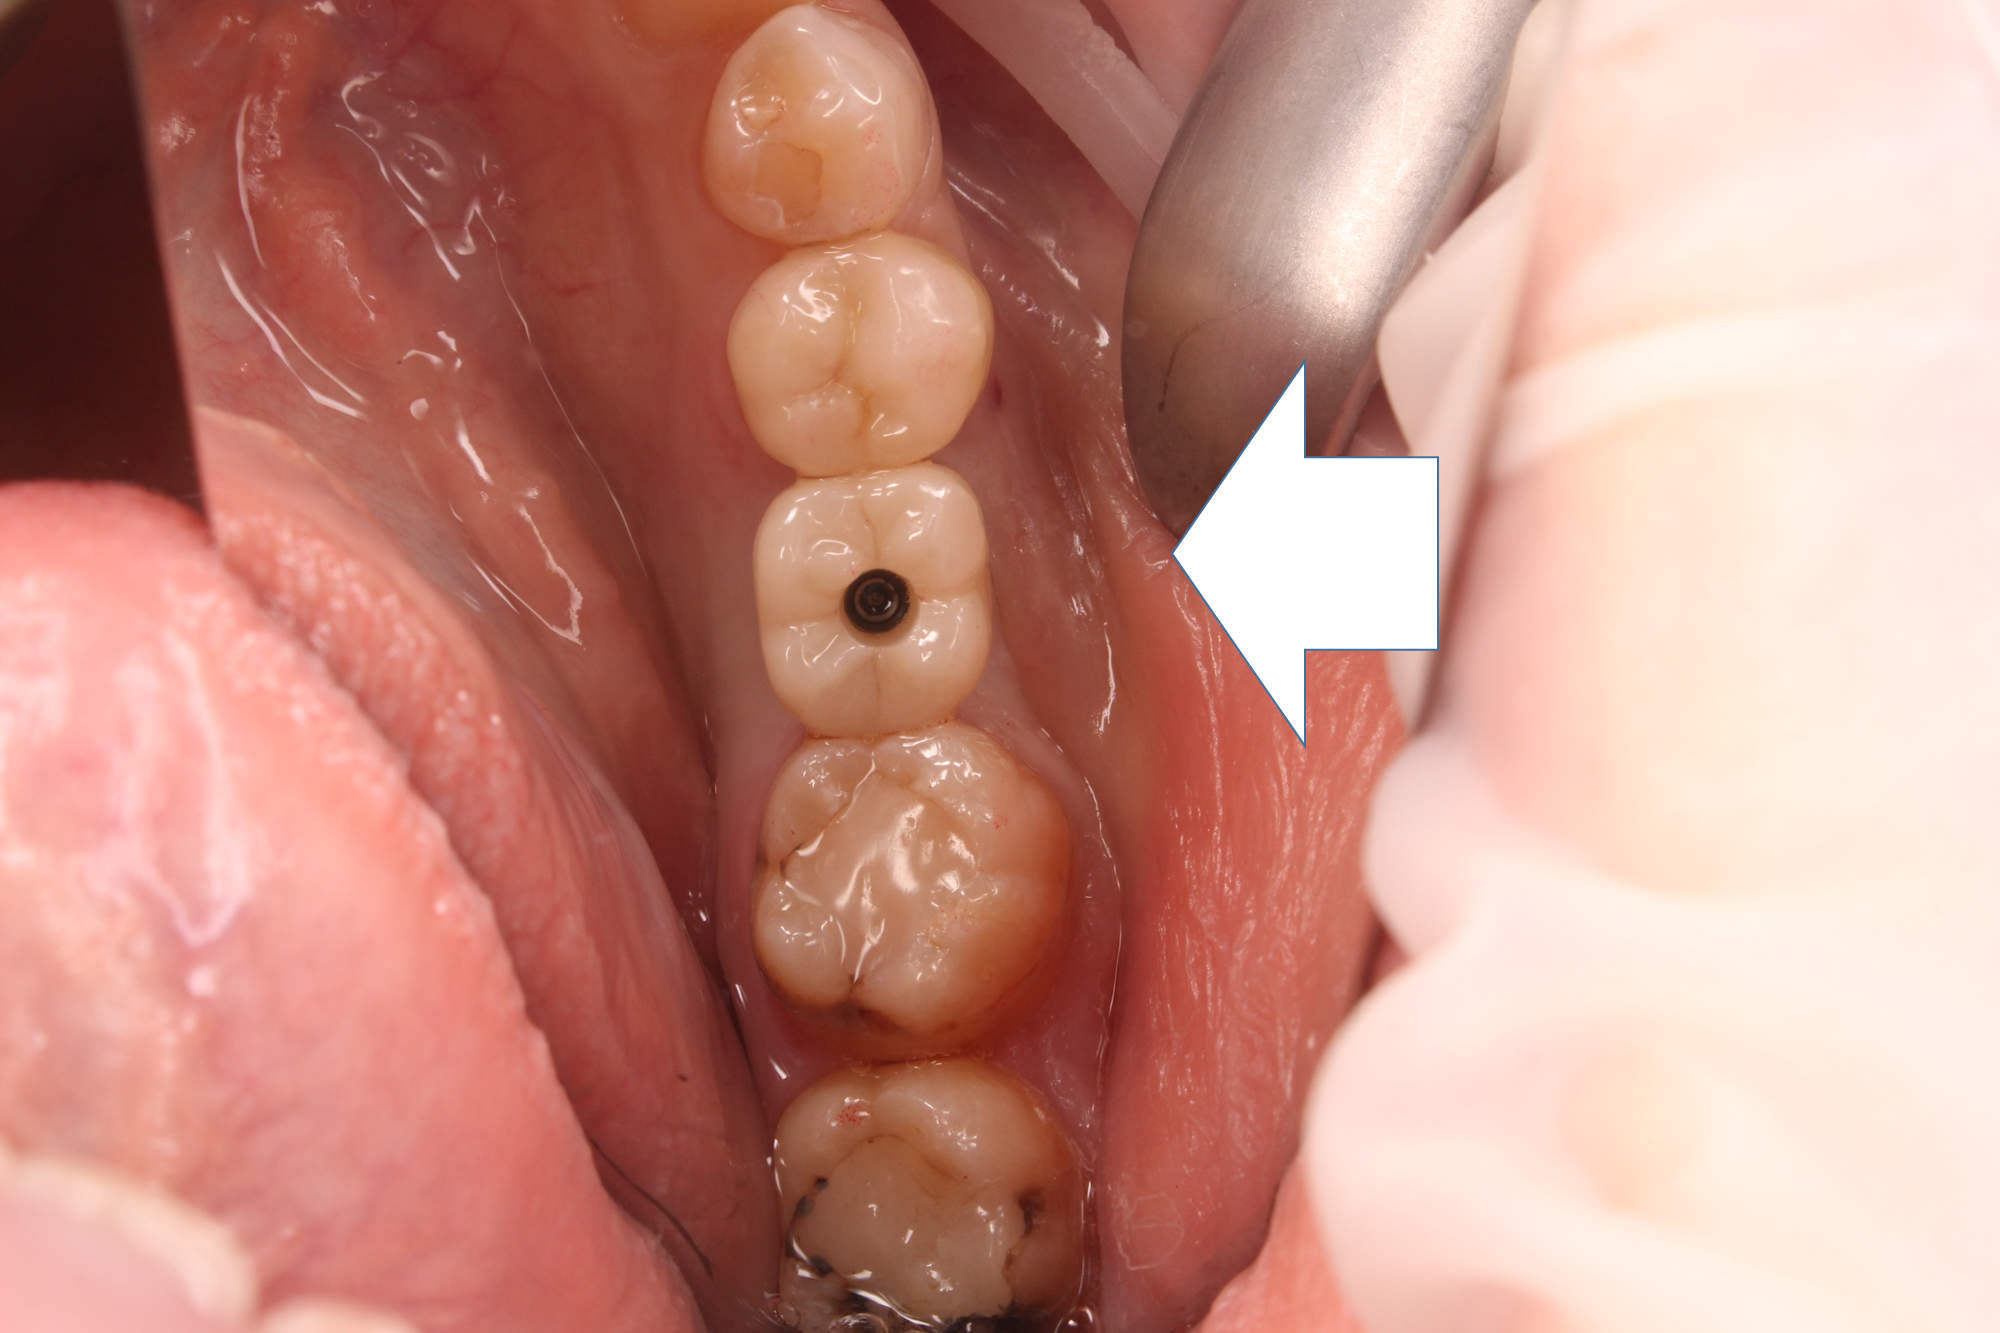

2次オペ後、約2週間の状態です。

2次オペ後、感染なども無く、経過も良好なので、この後インプラントの型どり(位置を正確に記録すること)を行い、上部構造を製作しました。

インプラント治療と並行して、患者さんから希望があった手前の歯の治療も行っています。

この歯は、幸い神経に感染がなかったのですが、虫歯が大きかったので、セラミックによる被せ物で対応しました。

完成した状態です。

無事、終了しました(^^)